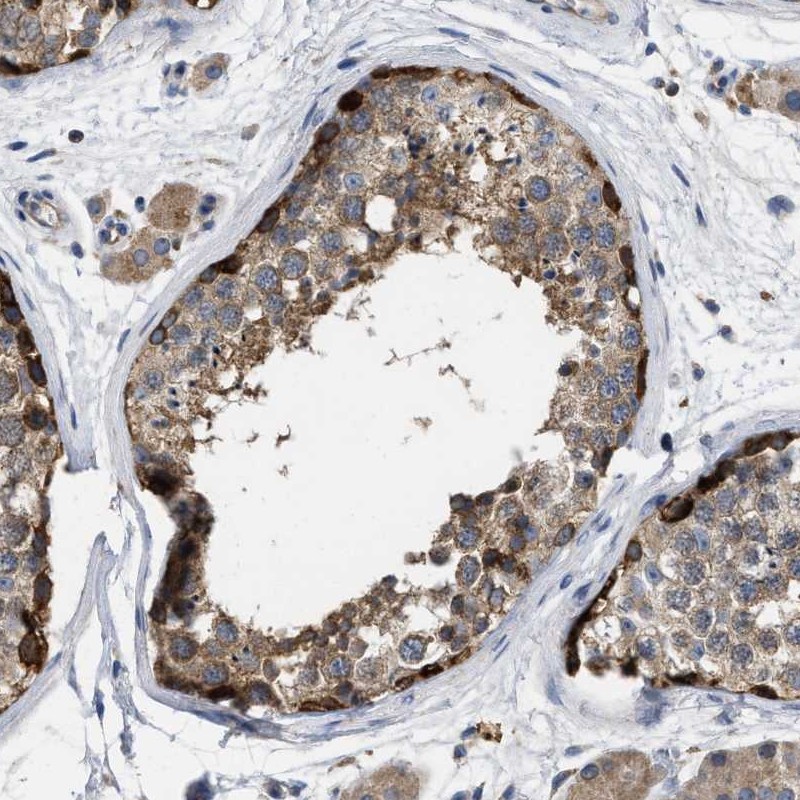

Immunohistochemical staining of human testis shows strong positivity in basal cells of the seminiferus ducts.